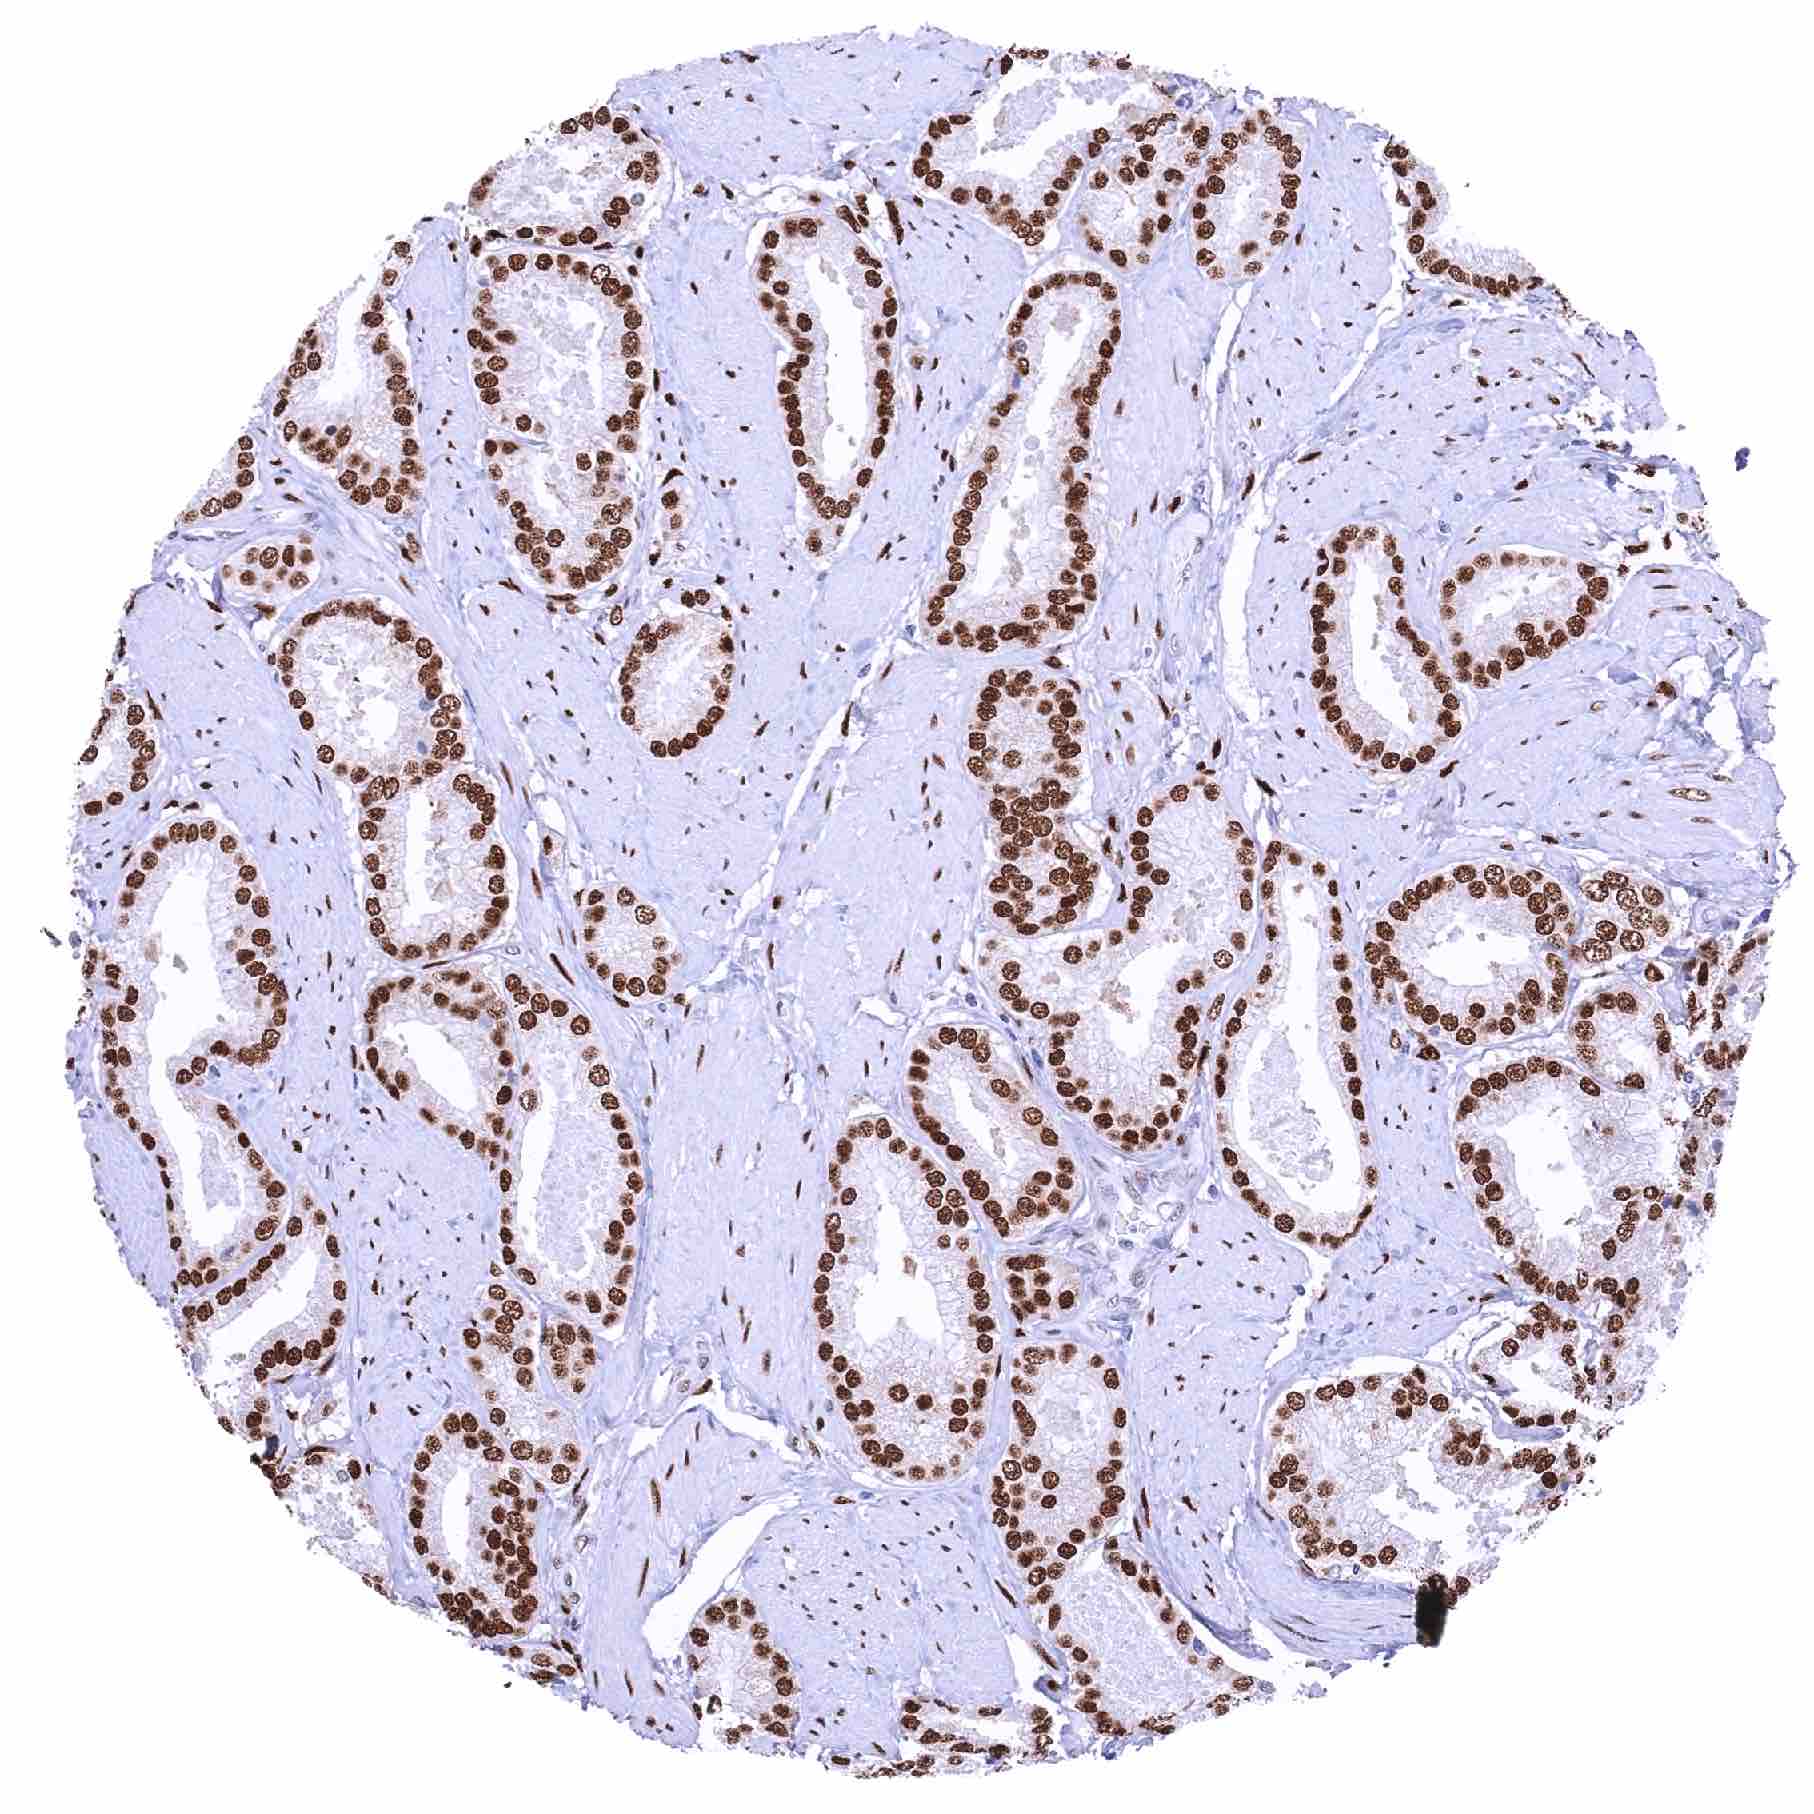

Prostate – Adenocarcinoma (Gleason 3+3=6) with strong NFIX staining of tumor cells